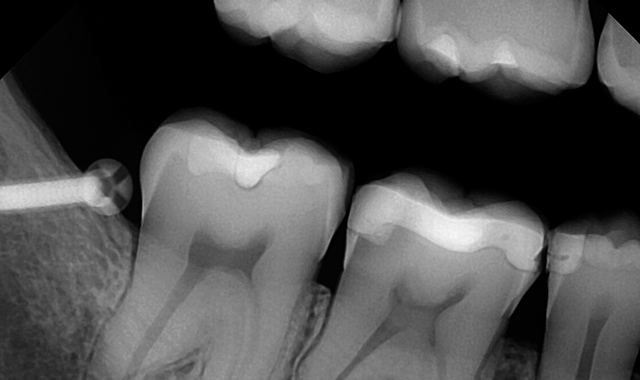

An example of a bad X-ray image

An example of a good X-ray image